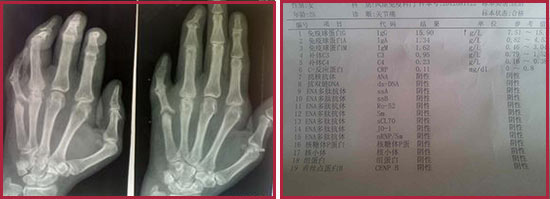

貴陽強直醫(yī)院類風(fēng)濕常規(guī)檢查.jpg

(圖:類風(fēng)濕性關(guān)節(jié)炎常規(guī)檢查容易出現(xiàn)誤診漏診的情況)

2、檢查方法過于陳舊:由于一些臨床醫(yī)師缺乏對類風(fēng)濕性關(guān)節(jié)炎特點的認識或只滿足于X線檢查,過分依賴骶髂關(guān)節(jié)的影像學(xué)檢查,而忽視類風(fēng)濕性關(guān)節(jié)炎的臨床表現(xiàn)和體格檢查,檢查過于簡單,無法科學(xué)的診斷病情,出現(xiàn)錯誤和遺漏,給治療造成障礙。